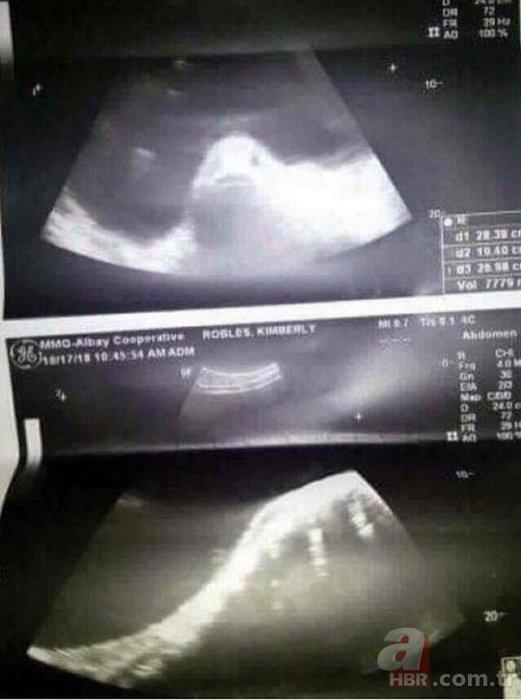

7News.Az xəbər verir ki, hadisə Filippində baş verib. Ötən ilin iyun ayında Kimberli Robles Besinal adlı gənc qız kəskin qarın ağrısıyla həkimə müraciət edib. Valideynləri onun sevgilisiylə yatdığını və hamilə qaldığını düşünərək qəzəblənib. Ancaq USM-də balığa bənzəyən görüntü ortaya çıxıb. Ailəsi də qızı balıqla cinsi əlaqəyə girməkdə günahlandırıb.

Aradan bir il keçsə də, doğum olmayıb. Növbəti yoxlama zamanı qızın yumurtalığında kista aşkarlanıb. Gənc qız da bu xəstəlikdən qurtulmaq üçün hazırda xeyriyyə kampaniyası başladıb.